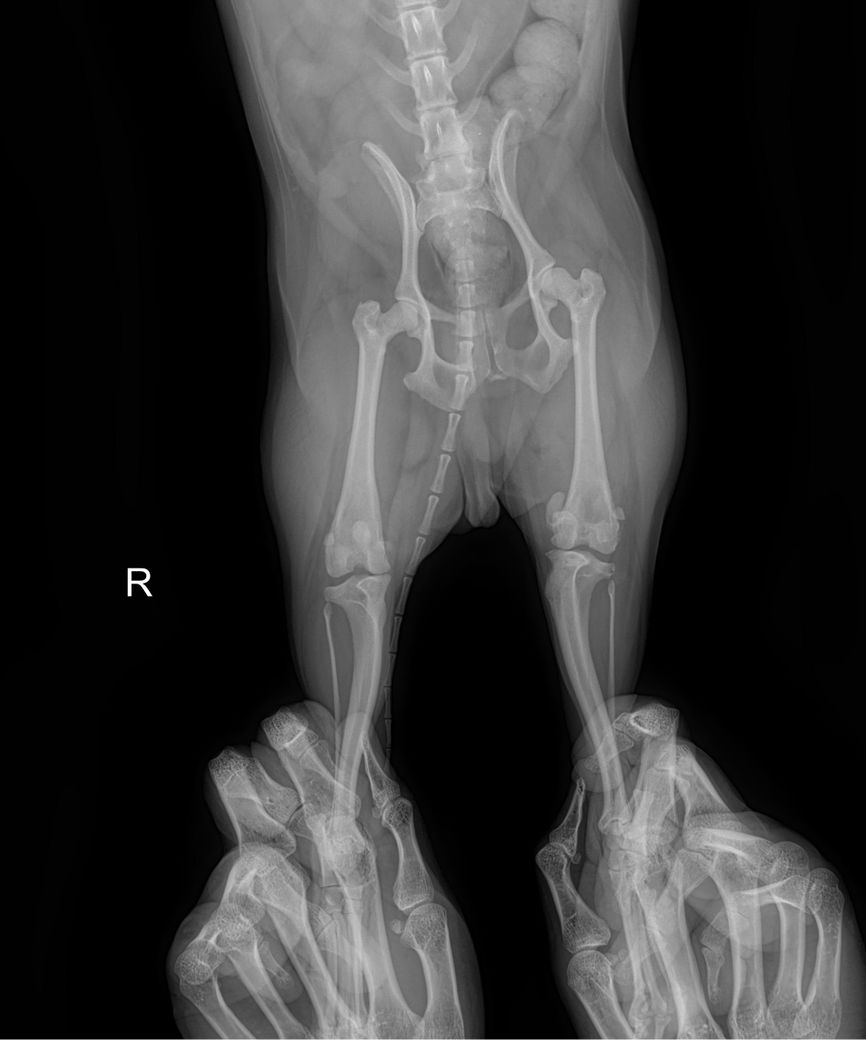

강아지 슬개골 탈구 엑스레이 봐주세요

제 반려견이 다리 한쪽이 아파보여서 병원 데려갔는데 뒷다리가 슬개골 탈구 심하다고 3기에서 4기로 넘어가고 있다고 하더라구요 이제 슬슬 수술 할려고 하는데 철심을 박아야 한다고 하더라구요 선생님들이 봐주셨을 때 정말 심해보이나요?ㅠㅠㅠㅠㅠ 왼쪽 , 오른쪽 중 어디인가요 너무 놀라서 헷갈려요 ㅠㅠ

좌측 슬개골이 내측으로 탈구되어 있는 상태이며.

외측상에서 슬관절 관절낭의 종창이 뚜렷하게 관찰되어 슬개골 탈구와 함께 십자인대의 부분적 손상 가능성이 강력히 의심됩니다. 주치의의 지시대로 빠르게 수술 진행하는게 도움이 됩니다.